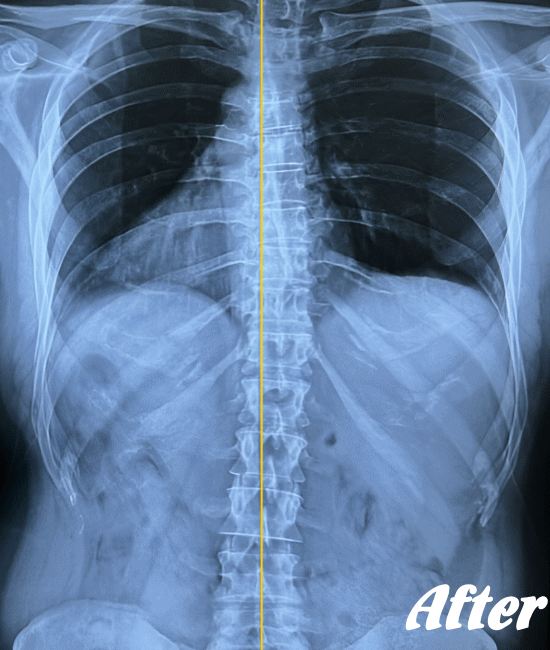

| 施術前(レントゲン) | 施術後(レントゲン) |

![]() |